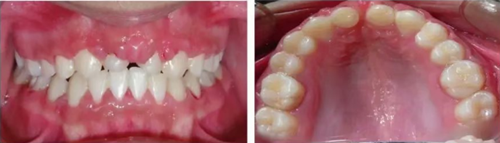

6個月后,移植牙的根尖片顯示治療期間沒有出現(xiàn)牙根吸收的影像?;颊邲]有出現(xiàn)不適,沒有發(fā)生牙齦炎。在23個月期間沒有進(jìn)行任何修復(fù)完成治療,達(dá)到I類關(guān)系(圖5和圖6)。

圖6. 正畸后口內(nèi)照